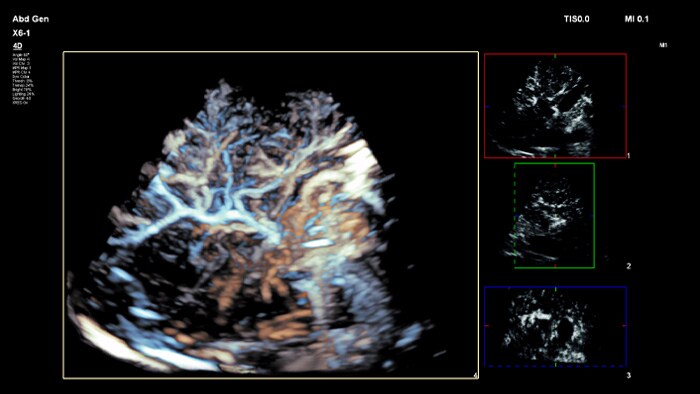

フィリップス、「Liver Fat Quantification(肝脂肪化定量評価。肝臓がん|消化器|診療内容|医療法人 甘木第一クリニック。肝臓がん|消化器|診療内容|医療法人 甘木第一クリニック。sakuraさん専用 蔵王吊るし柿4kg 紅干し柿 600g。Contrast Enhanced Ultrasound (CEUS) | フィリップスヘルスケア。Liver Ultrasonography | SpringerLink。キヤノンメディカルシステムズ、『肝臓の脂肪量の汎用超音波画像。Imaging Features of Hepatocellular Carcinoma in the Non。Imaging Features of Hepatocellular Carcinoma in the Non。714cFtk9QyL._AC_UF350,。肝臓病変における超音波の最新情報-第24回腹部放射線研究会。KMS_M01_XXX_670.jpg。腹部の超音波検査健康なヒト胆嚢 - 胆嚢のストックフォトや画像。